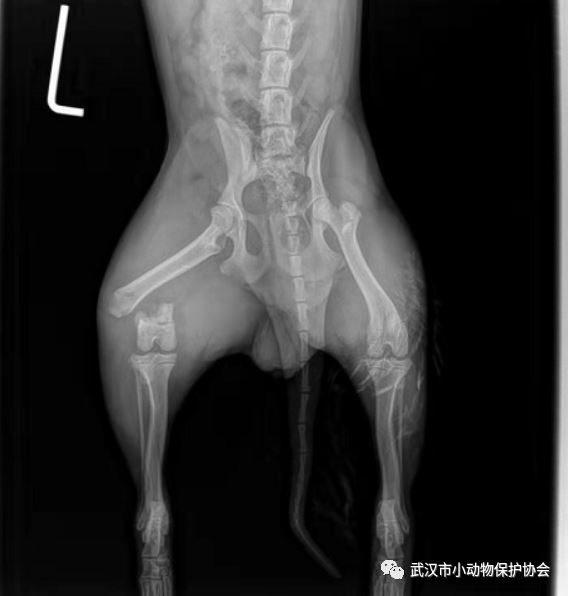

经过X光检查,狗狗大腿骨折,脚掌粉碎性骨折,住院观察期间伴有拉血,好在狗狗很顽强,拉肚子治疗好了,两次骨科手术也很成功。